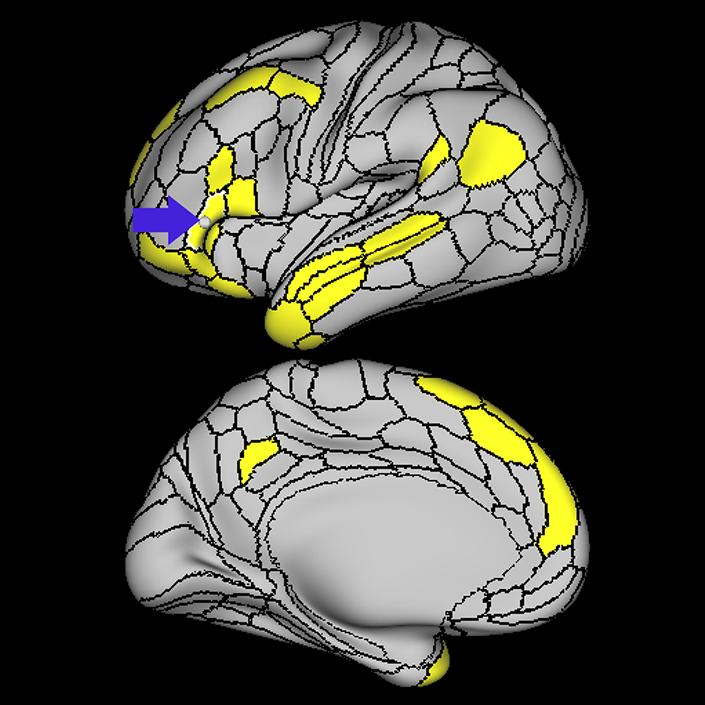

ᐅ SummaryArea 44: part of the inferior frontal gyrus of the lateral frontal lobe. Translates abstract and intentional information in the prefrontal cortex to more detailed representations to help guide the production of verbal and manual actions. In addition to its known association with Broca's area, is sometimes represented as part of Broca's complex ᐅ Where is it?Area 44 is at the posterior most part of the inferior frontal gyrus. It is the anterior bank of pars opercularis of the IFG. ᐅ What are its borders?Area 44 borders area 45 anteriorly and area 6r posteriorly. Area 8C is its medial border and its inferior border is wedged between then upper borders of Areas 6R and 6V. Its superior edge borders IFSp and IFJa. Its opercular surface is FOP4. ᐅ What are its functional connections?Area 44 demonstrates functional connectivity to areas SFL, IFSp, IFJa, 45, 47s, 47L, 9a, 9m, 8AV, 8BL and 8C in the dorsolateral frontal lobe, area 8BM in the medial frontal lobe, area 55b in the premotor areas, areas FOP5, AVI and PSL in the insula- opercular region, areas TGd, STSdp and STSvp in the temporal lobe, areas PFm, and PGi in the inferior parietal lobe, and no areas in the medial parietal lobe. ᐅ What are its white matter connections?Area 44 is structurally connected to the arcuate/SLF and the FAT. Connections with the arcuate/SLF project posteriorly and wrap around the Sylvian fissure to the middle temporal gyrus to end at TE1a and TE1m. There are also projections from the arcuate/SLF before it terminates to parcellations A5 and STSdp. The majority of the inferior connections of the frontal aslant tract end at 44, the tract is connected superiorly to superior frontal gyrus parcellations SFL, 6ma and s6-8. Local short association bundles are connected with 45 and 8C. White matter tracts from 44 in the right hemisphere have less consistent connections with the arcuate/SLF. ᐅ What is known about its function?Area 44 translates abstract and intentional information in the prefrontal cortex to more detailed representations to help guide the production of verbal and manual actions. Area 44, in addition to its known association with Broca's area, is sometimes represented as part of "Broca's complex", including Brodmann Areas 45, 46, 47 and the mesial supplementary motor area of 6, which contribute to a frontal-subcortical circuit. The right pars opercularis has also been implicated in cognitive inhibition in the overall context of working memory. |

A: lateral-medial

B: anterior-posterior

C: superior-inferior

DTI image |